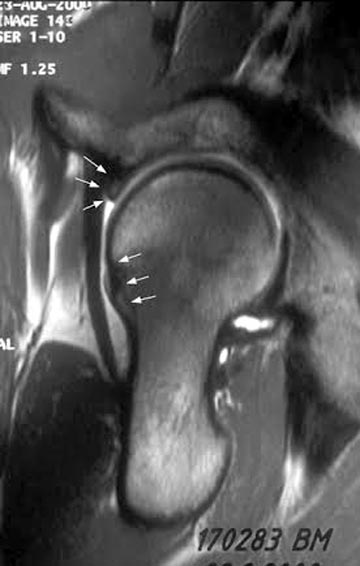

Обычно при внутрикостной кисте болевой симптом не проявляется, но

капсула и лабральное кольцо из-за измененной анатомии могут быть

причиной боли! Хроническая травма на шейке образует характерный бугор,

меняется центр ротации, и во время нагрузки бугор выталкивает головку из

вертлужной впадины. Это приводит к деламинации хряща, что не всегда

определяется на рентген снимке. Поэтому следующим методом исследования

становится МРТ с гадолинием, потому что другие исследования не покажут

состояние лабриум и хряща!

Здесь представлены рентген, боковой, МРТ и клинические снимки

деламинации хряща одного того же пациента.

Имя     : Hip Impingement MRI.jpg

Тип     : image/jpeg

Размер  : 38764 байтов

Описание: отсутствует

Url     : http://weborto.net:8080/pipermail/ortho/attachments/20160418/78e1d55d/attachment-0007.jpg